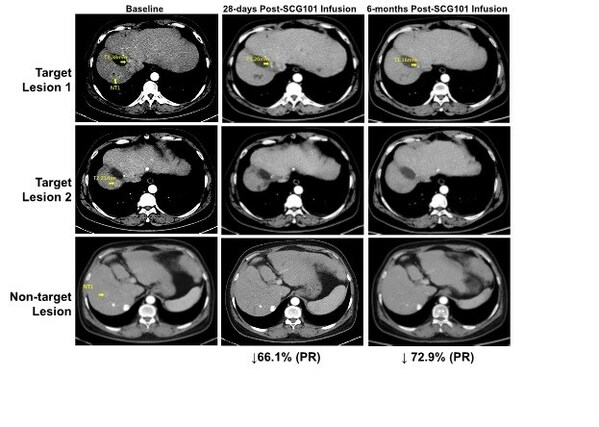

臨床數據顯示,SCG101具有顯著的抗腫瘤和抗病毒活性,一名患有乙型肝炎病毒(HBV)相關肝細胞癌(HCC)患者接受單劑SCG101輸注後,第28天腫瘤靶病灶相比基線縮小66%,達到部分緩解(PR),並在第4個月進一步縮小74.5%;另一處病灶完全消失。試驗期間患者沒有接受任何其他抗腫瘤治療。數據截止時,腫瘤已保持超過6.9個月沒有進展,保持持續緩解狀態。